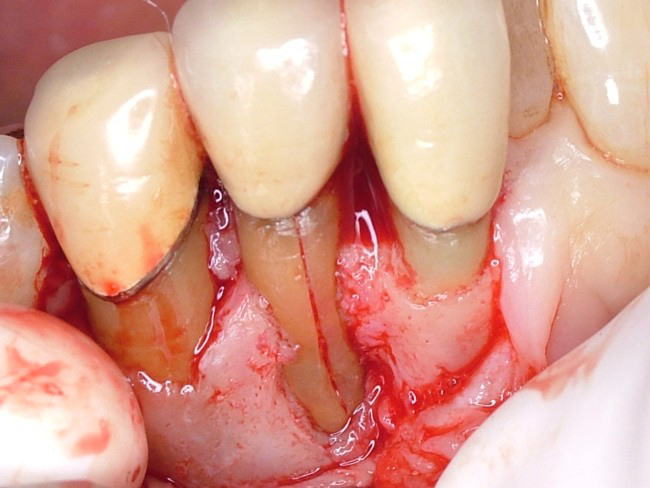

下の写真は右下の側切歯の歯根破折です。真ん中の歯の歯根中央に破折線をご覧いただけると思います。

またついでながら両隣の歯には歯周病による著しい歯槽骨吸収が見られます。歯根破折の原因は様々ですが、写真のケースの場合はかぶせ物をする際にすでに失われた歯質を補うために歯根中央に埋め込んだポストと呼ばれる金属製の心棒が災いしたと思われます。

冠に加わる咬合圧が金属の心棒に伝わり、その分力が歯根を割る方向に働いたのではないか、ということです。処置としては抜歯適用ですがケースによっては接着技術の適用によって抜歯を避けることも可能です。